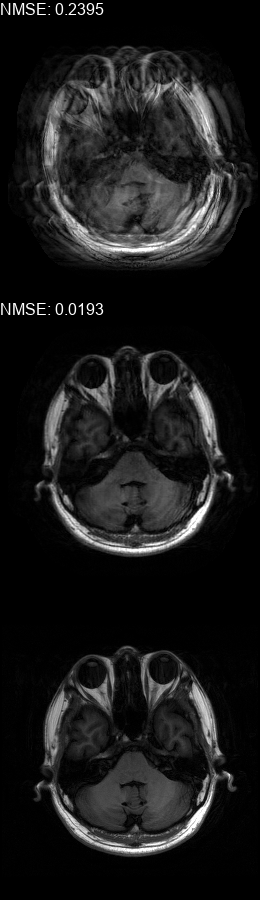

Results  Experimental results using the two presented datasets, for the fully-sampled and under-sampled k𝑘k-space scan orders, are shown in Table 1. The table presents the Normalized Mean Square Error (NMSE) obtained for each of the scan orders. For the Transaxial dataset, we only show the results for the challenging task where the DP contains only up to 707070 columns of k𝑘k-space data. All methods are able to reduce the NMSE of the corrupted scans, however the methods that incorporate the DC layer achieve a much better result. These results match our subjective visual impression of the motion-corrected images, as may be seen in Fig. 3 for simulated motion in a fully-sampled k𝑘k-space data, and Fig. 4 for an under-sampled k𝑘k-space data.

Figure 4: Motion corrected images from the Diverse dataset calculated using the 𝒰𝒮260𝒰subscript𝒮260\mathcal{US}_{260} scan order presented in Fig. 1c. The bottom row shows the fully-sampled motion-free images. The top row shows the under-sampled motion-corrupted images used as input to the correction method, these images show an additional aliasing artefacts in comparison to the ones in the top row of Fig. 3 since they are missing approximately half of the k𝑘k-space data. The middle row shows the corrected images calculated using our method. (a) contains two motions at t1=79subscript𝑡179t_{1}\!=\!79, t2=132subscript𝑡2132t_{2}\!=\!132, (b) contains a motion at t1=61subscript𝑡161t_{1}\!=\!61, (c) contains a motion at t1=83subscript𝑡183t_{1}\!=\!83, (d) contains two motions at t1=78subscript𝑡178t_{1}\!=\!78, t2=123subscript𝑡2123t_{2}\!=\!123, (e) contains three motions at t1=13subscript𝑡113t_{1}\!=\!13, t2=97subscript𝑡297t_{2}\!=\!97, t3=127subscript𝑡3127t_{3}\!=\!127, (f) contains two motions at t1=55subscript𝑡155t_{1}\!=\!55, t2=128subscript𝑡2128t_{2}\!=\!128.